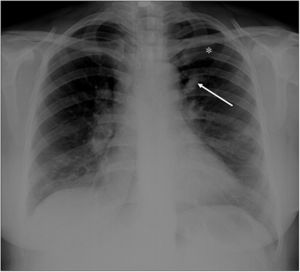

A 22-year-old woman was referred to our emergency radiology unit with sudden onset of shortness of breath and left-sided chest pain. The chest radiography revealed left hilar tubular opacite (arrow) and hyperaeration (asterisk) in the upper zone of the left lung (Fig. 1). The contrast enhanced computed tomography (CT) showed a non-contrast enhancing tubular mass that was seen extending from the left hilum, with surrounding hypoattenuation of the apicoposterior segment of the left upper lobe (asterisk), a finding indicative of hyperinflation (Fig. 2A). There was also no connection between the non-contrast tubular mass (arrows) and pulmonary artery of the apicoposterior segment in the left upper lobe (Fig. 2B–C). CT findings were also including mucocele and occlusion of the bronchus central to the mucocele. CT results (mucocele with hyperaeration of the adjacent lung parenchyma) were considered pathognomonic for bronchial atresia. Surgical treatment was no performed because the patient refused operation.

Radiologically, bronchial atresia is associated with a triad of findings: focal interruption of a bronchus; associated distal mucus impaction (bronchocele) that is visible as a branching tubular or ovoid area of increased attenuation; and associated hyperinflation of the obstructed pulmonary segment.2 Bronchial atresia should be kept in mind in patients with shortness of breath and chest pain.